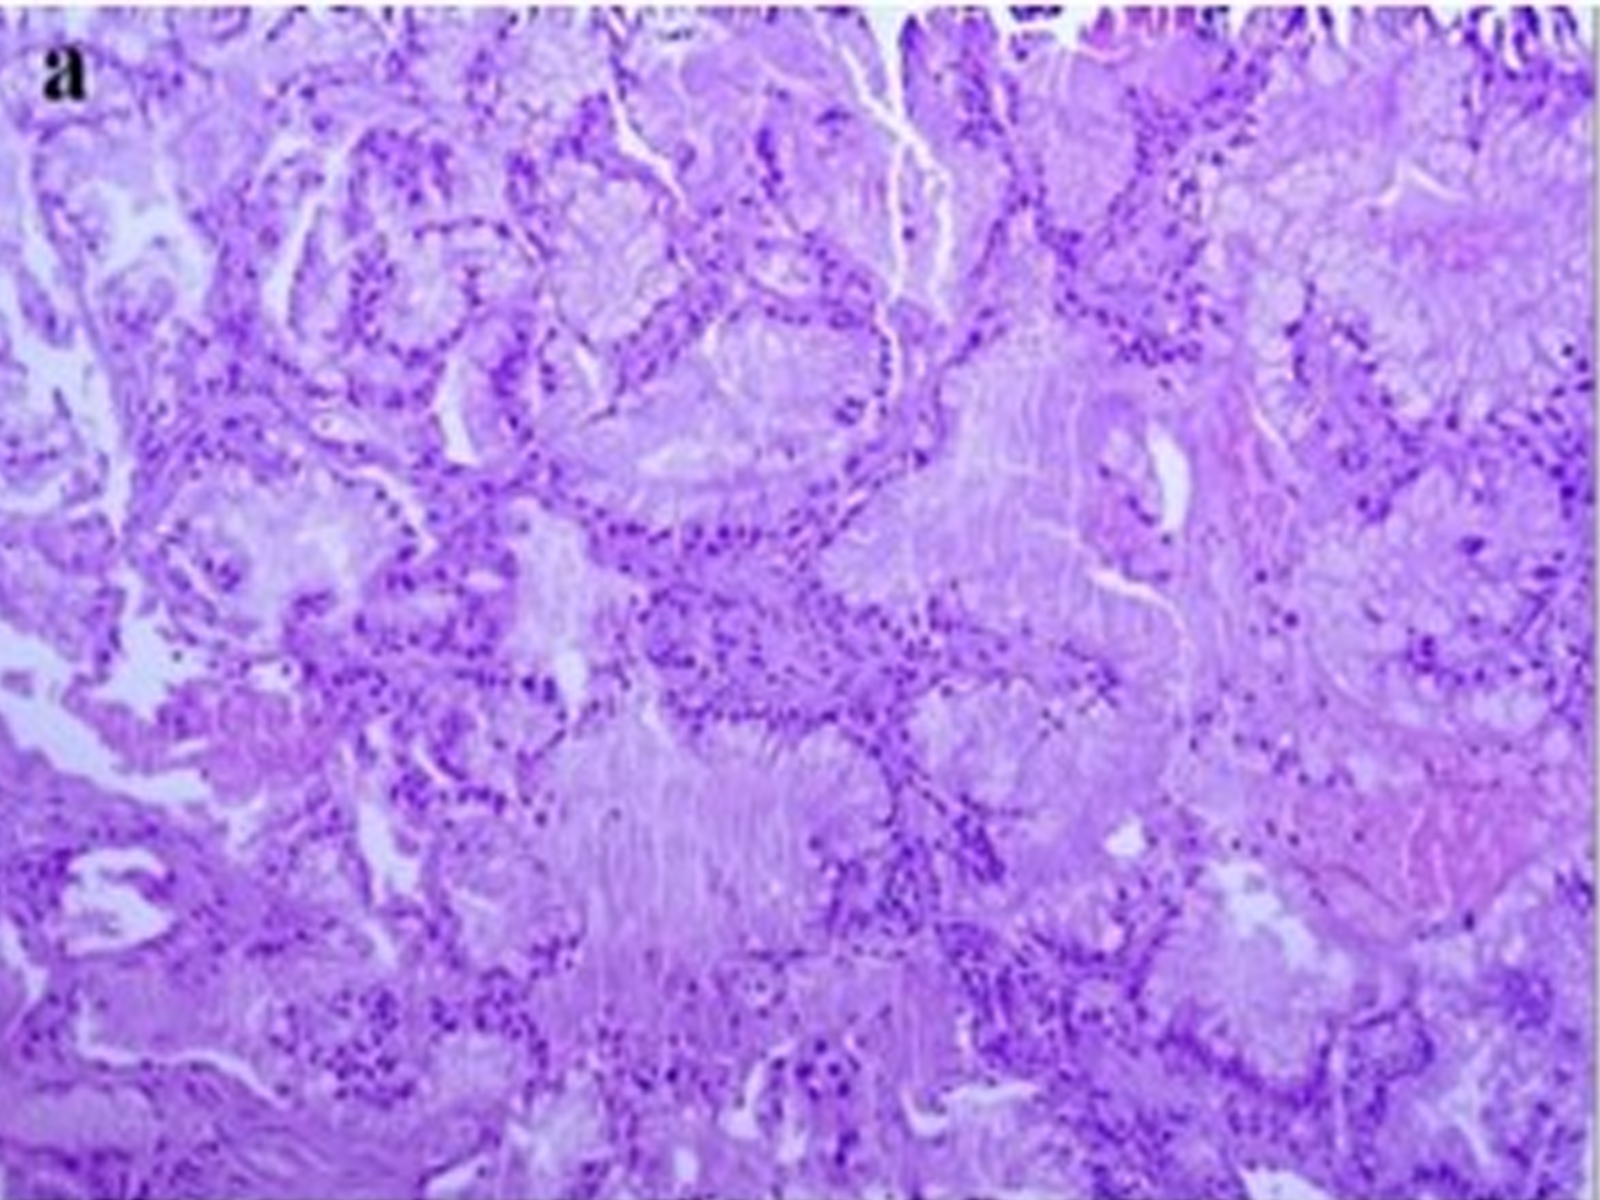

Infectious Masquerade: Mucinous Adenocarcinoma of the Lung Presenting as Pneumonia

Ashok Arbat, Diti Gandhasiri, Sweta Chourasia, Swapnil Bakamwar, Parimal Deshpande doi: 10.5505/respircase.2026.83446 Pages 43 - 46 |